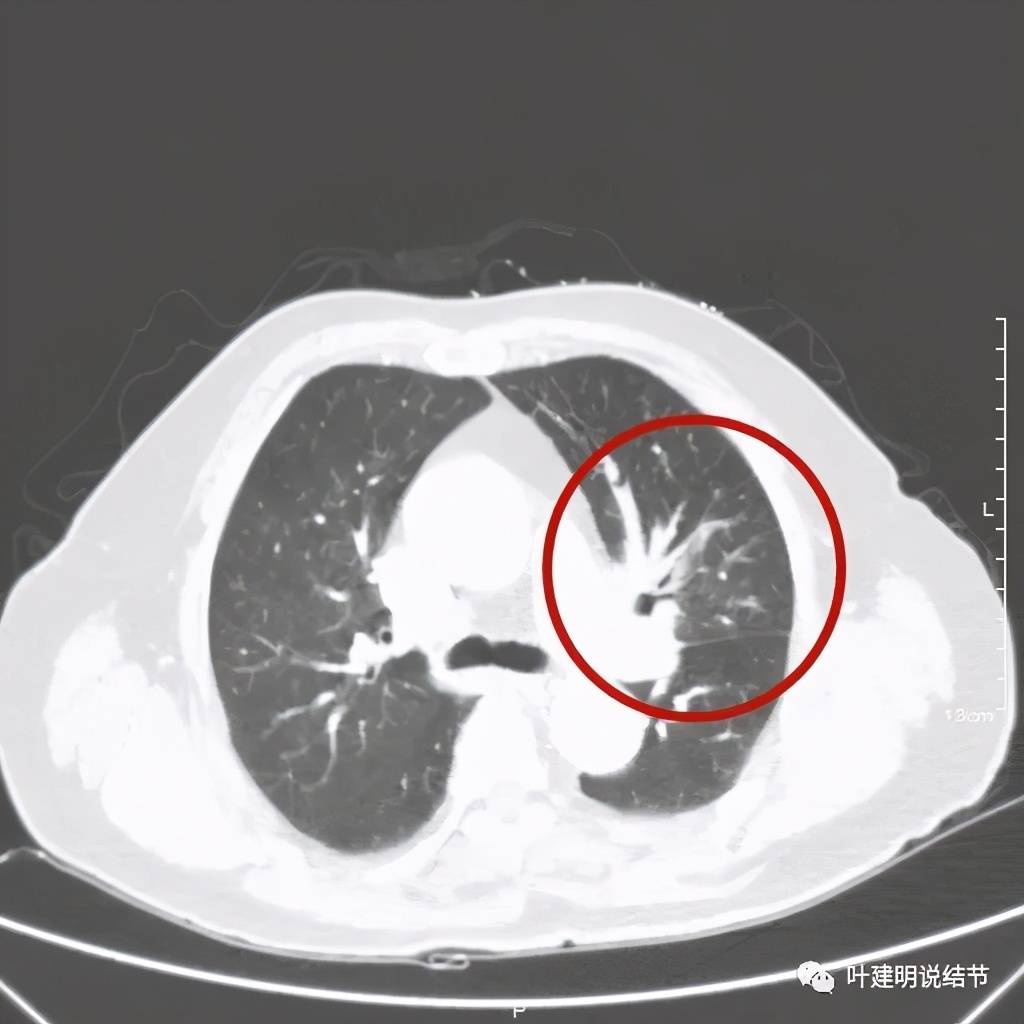

肺窗见原左上叶巨大占位已经明显缩小,甚至几乎不见了!而且上图示左上叶支气管清晰可见,内壁变光滑。纵隔窗增强又是如何的呢?